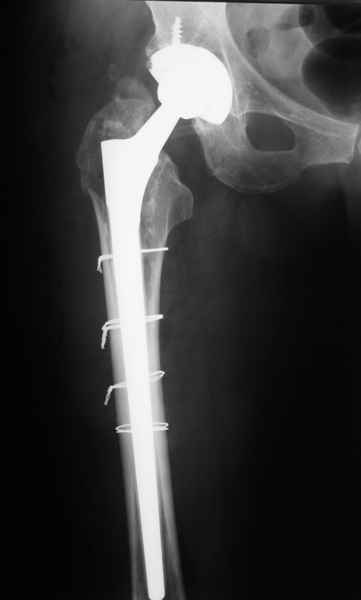

2. Применение ножки дистальной фиксации, мы отдаем предпочтение ножке Вагнера с фиксацией проксимального отдела на ножке. Более травматичное вмешательство, но при стабильной фиксации ножки реабилитация идет в обычном режиме.

Хочется показать два подобных случая, П-ка З. 72 лет и п-т Г. 80 лет. Сразу принимаю замечание, что это были ножки цементной фиксации, просто под руками не было бесцементника.

С уважением, Р.Тихилов